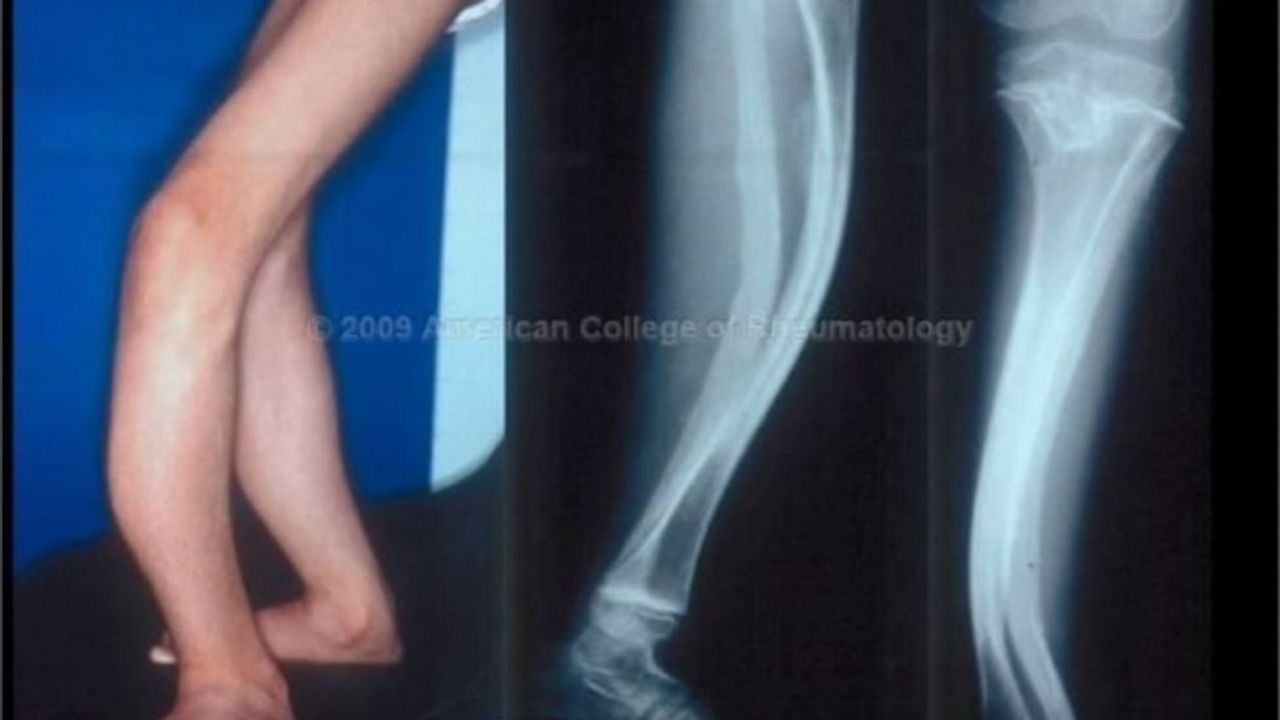

Несовершенный остеогенез типы

Несовершенный остеогенез типы 112 фотографий